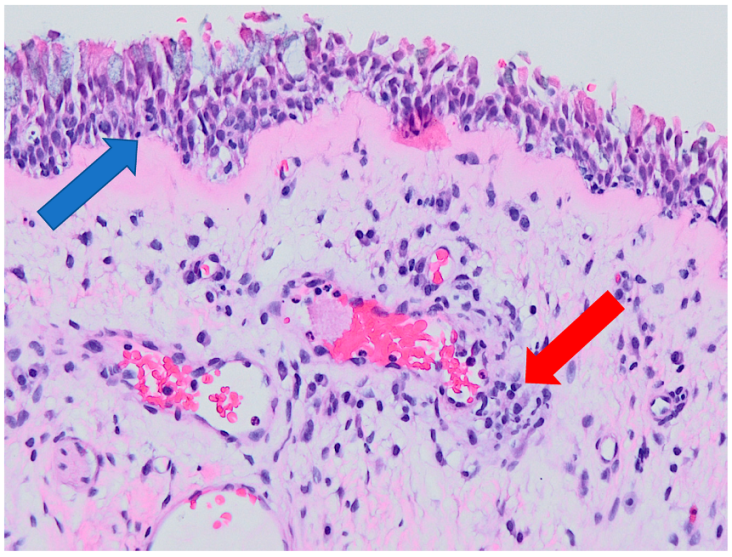

- 0

- Chronic inflammation.

3.2. Histology

3.3. Correlation of Histology and Detected Compounds

3.4. Correlation of Smoking Status and Detected Compounds

3.5. Correlation of Occupational History and Detected Compounds

4. Discussion